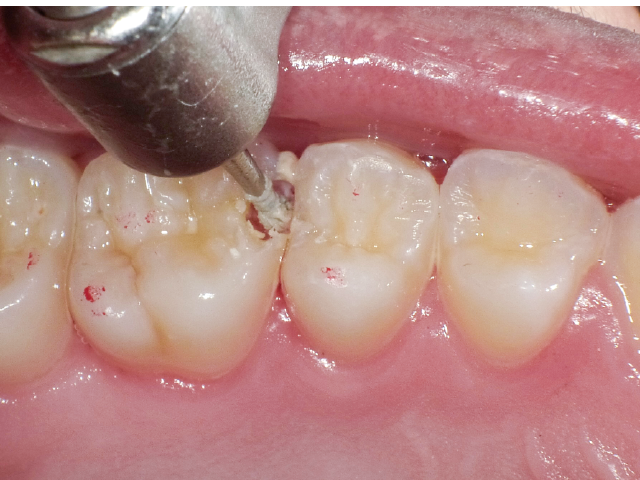

修復治療の第一段階として特に意識して行うべきステップは、感染歯質の除去に限定した、可能な限り最小化した窩洞形態の付与であり、それにより健全歯質の温存と修復規模の縮小に務めることが必要です。そのため、この場面で窩洞形成に用いる切削器材の選択は大変重要で、う窩の開拡、感染歯質の除去、窩縁部の仕上げなど、窩洞形成の各ステップで術者が意識して器材を使い分ける必要があります。

本稿では、最小限の健全歯質除去でう窩の開拡を行い、う蝕検知液を併用して感染象牙質に限定したう蝕除去を徹底し、最終的には隣在歯の誤切削防止が可能なエアースケーラーチップにより窩洞形成を仕上げた症例を示しながら、いかにして今日求められるMI修復を実現していくべきかを提示していきます。

臼歯部隣接面における初期う蝕治療では、適切なタイミングで治療に介入し、充填操作の行いやすい環境で窩洞形成を終えることが、最終的な修復の長期予後を左右します。う蝕が象牙質に進行することにより、エナメル‐象牙境におけるう蝕の範囲拡大が起き、その程度により修復難易度が決定されます。よって頬舌側の隅角部の残存歯質量と歯肉側窩縁のエナメル質残存量が重要となります。

本症例では窩洞底部のエナメル質窩縁への窩洞形成の最終仕上げに硬組織の繊細な切削が可能なエアースケーラーチップを活用し不用意な窩洞規模の拡大を防ぐことができました。それにより、シンプルなマトリックスシステムでの隣接面部への精密な充填操作が可能となり、修復の長期予後に期待がもてる状況となりました。精度の高いMIコンポジットレジン修復において、エアースケーラー専用のダイヤモンドチップが非常に相性が良いことが確認されました。このような切削システムを有効に活用することで、より精密で長期的な修復結果が得られる可能性が高いと考えます。